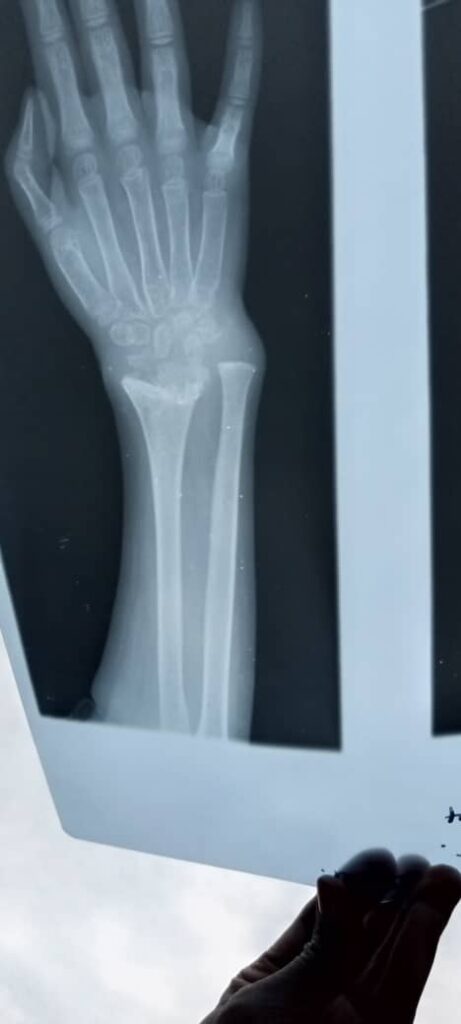

Esther somehow managed to miraculously escape. She survived but sustained a bullet wound to her left hand.

Part of that care includes a much-needed operation on her left hand. The injury is painful and has left her feeling embarrassed at times when she’s around other children. Surgery would help to restore her left hand’s functionality.